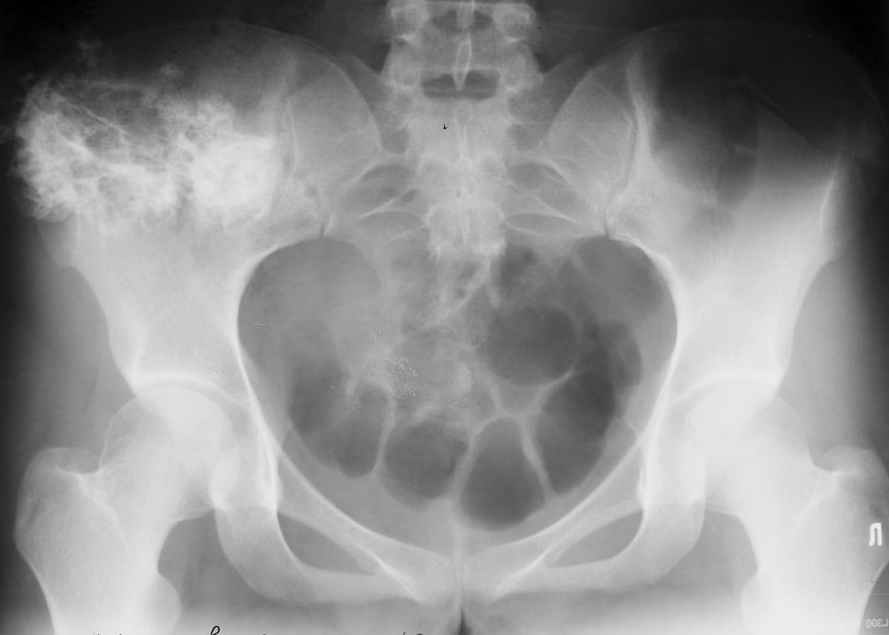

Уважаемые коллеги! К нам поступила пациентка 16 лет с диагнозом: остеохондрома крыла правой подвздошной кости.

Учитывая большие размеры образования, необходимо удаление его с резекцией крыла подздошной кости вместе с ее гребнем. Предполагается наличие большого дефекта. Поделитесь опытом закрытия таких дефектов.

Судя по КТ, проблема не в гребне а в крыле...

Опухоль имеет задне-наружное нправление...

По-моему, КТ-картина наводит на мысль об озлокачествлении (резкая неоднородность, местами размытие контуров) - вторичной хондросаркоме. Местами, кстати, имеется рост и в направлении брюшной полости. Для решения вопроса об объеме резекции в данном случае оправдана трепанобиопсия. Если это хондросаркома, особенно низкодифференцированная, то стоит обсудить возможность удаления всего крыла с окружающими мягкими тканями. Вариант реконструкции - комбинированная пластика аллотрансплантатами. А вот какими - зависит от наличия костного банка и возможностью индивидуального изготовления трансплантатов. При отсутствии таковой не лучше ли направить ее в ЦИТО?